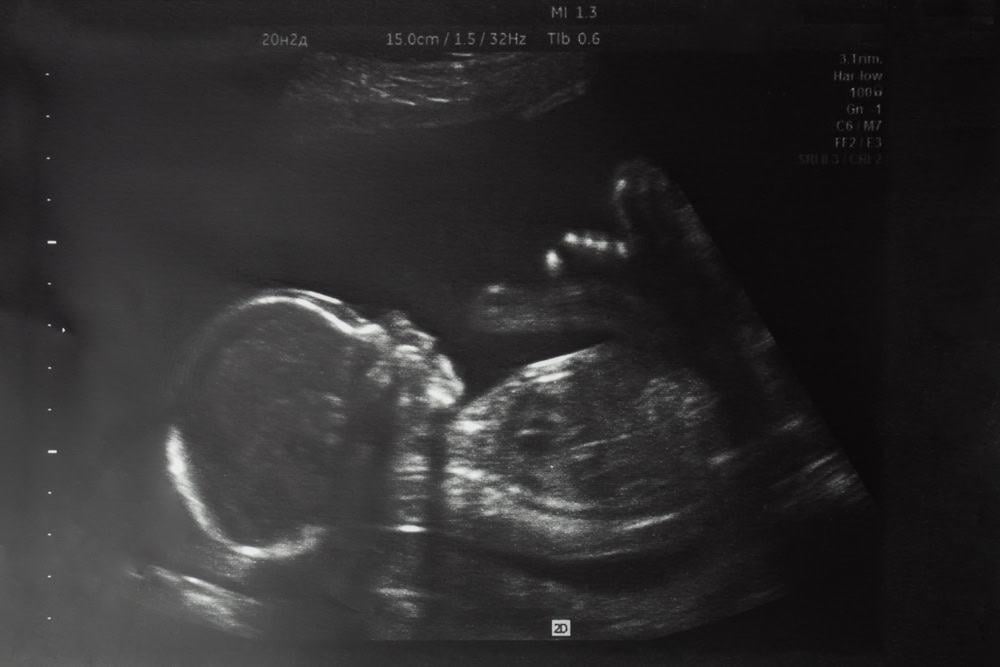

Mẹ bầu chỉ có thể biết được chính xác tư thế nằm của thai nhi 30 tuần, cũng như biết thai nhi 30 tuần tuổi đã quay đầu chưa bằng phương pháp siêu âm doppler, siêu âm 2D, 3D hay 4D.